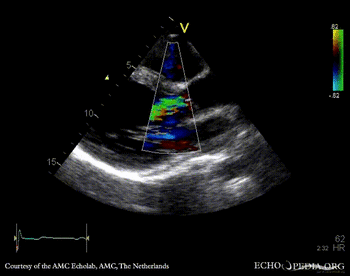

E00339.gif E00340.gif

PLAX: thickend aortic valve PLAX: Color Doppler, moderate aortic regurgitation